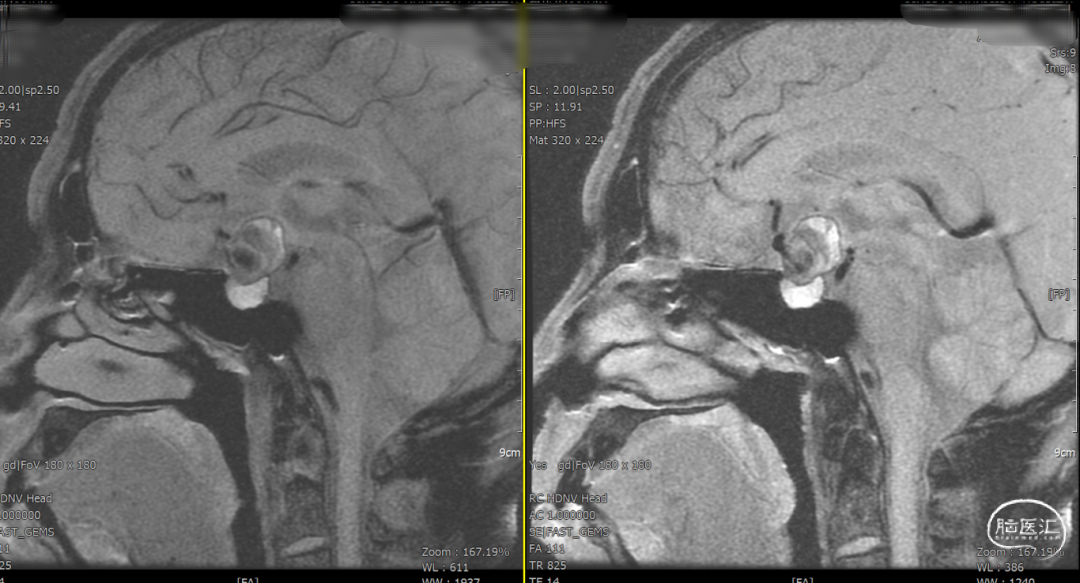

辅助检查示:2025-01-08 鞍区及垂体MR平扫:鞍内及鞍上肿瘤,垂体瘤并卒中?建议鞍区及垂体MR增强扫描。

2025-1-19 DSA造影3D重建及方案讨论: